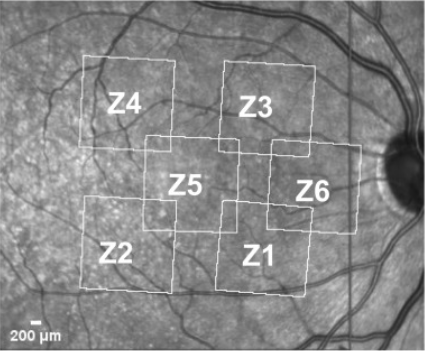

Govindahari V., Dornier R., Ferdowsi S., Moser C., Mantel I., Behar-Cohen F., Kowalczuk L., High-Resolution Adaptive Optics-Trans-scleral Flood Illumination (AO-TFI) Imaging of Retinal Pigment Epithelium (RPE) in Central Serous Chorioretinopathy (CSCR), Scientific Reports, 14.1 (2024):13689. doi: 10.1038/s41598-024-64524-4. |

Kowalczuk L., Dornier R., Kunzi M., Iskandar A., Misutkova Z., Gryczka A., Navarro A., Jeunet F., Mantel I., Behar-Cohen F., Laforest T., Moser C., in vivo Retinal Pigment Epithelium Imaging using Transscleral OPtical Imaging in healthy eyes, Ophthalmology Science, 100234 (2022). |